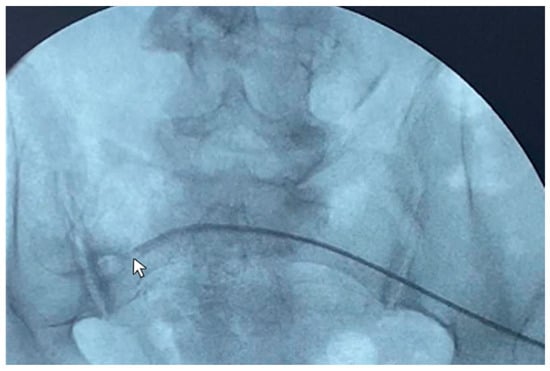

A 77-year-old male patient with ESKD secondary to diabetic kidney disease underwent placement of a “Vicenza Short”peritoneal catheter by open surgical dissection under local anesthesia. Peritoneal dialysis was started after two weeks, but poor drainage performance with a large residual volume was immediately observed. An abdominal X-ray documented coprostasis and the right location of the peritoneal catheter tip in the pelvis. The patient tried different laxatives and enemas without improvement in the outflow performance of the catheter. The patient underwent catheterography that demonstrated regular inflow but impeded outflow function. The catheter appeared to be stuck on the postero-lateral side of the iliac right region (Figure 2), and wire-guided manipulations failed to move it from its original position. The patient reported mild pain after the procedure that was easily relieved with oral acetaminophen.

The CT abdomen scans disclosed adipose tissue entrapping the peritoneal catheter near its insertion in the abdominal cavity and the tip being right before the bladder wall. Considering the patient’s comorbidities, he was not eligible for videolaparoscopic rescue and thus was subjected to peritoneal catheter removal and replacement with a longer one (Vicenza) through a mini-laparotomy surgery. This catheter showed better hydraulic function and allowed the patient to finally perform adequate peritoneal dialysis.

In this case, catheterography failed to diagnose the cause of malfunctioning, and the CT scan lateral film aided it.

Figure 2. Catheterography showing the peritoneal catheter with the tip (Life 14 01475 i002) ending in the right iliac region.